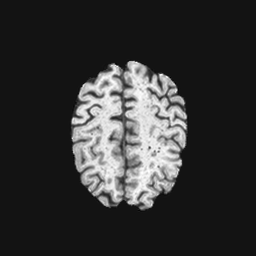

Exp. 2: Fetal brain data is used to test the robustness of our approach under real conditions. Fetuses younger than 30 weeks very often move a lot during examination. Fast MRI sequences allow artifact free acquisition of individual slices but motion between slices corrupts consistent 3D information. Fig. 3 shows that our method is able to accurately predict also under these conditions. For this experiment we use from three orthogonally overlapping stacks of ssFSE slices covering the fetal brain with approximately 20-30 slices each. We are ignoring the stack transformations relative to the scanner and treat each individually. For , 28 clinically approved motion compensated brain reconstructions are resampled into a volume with spacing. A density of 500 unique sampling normals has been chosen via the Fibonacci sphere sampling method with 25 sampling planes evenly spaced between -25 to +25 on the Z-axis. This gives a plane spacing of 2mm, sampling only the middle portion of the fetal brain. Training took approximately 10hrs for 30 epochs. Prediction, i.e., the forward pass through the network, takes approx. 12 ms/slice.

0..5 Randomly selected illustrative inference results

Here we show for Exp. 1, Exp. 2, and Exp. 3 randomly selected examples of images that have been presented to the network (ground truth) compared to an image sampled at the predicted location.

In these experiments, we present a ground truth (GT) image to the network to estimate the respective transformation parameters needed to reorient the slice in its correct world co-ordinates. Using the transformation parameters, we generated a slice from the 3D atlas in the location where the network has predicted that slice should be (denoted as SVRNet).

The slices are compared side-by-side to give a visual representation of “where the slice really is” and “where the network thinks the slice is”.

0..5.2 Exp. 2:

Slices, from a motion corrupted MRI stack, are segmented and cropped. Since there is no ground truth for the queried images, an arbitrary fetal atlas is used for visualization in Fig. 11 and 12.